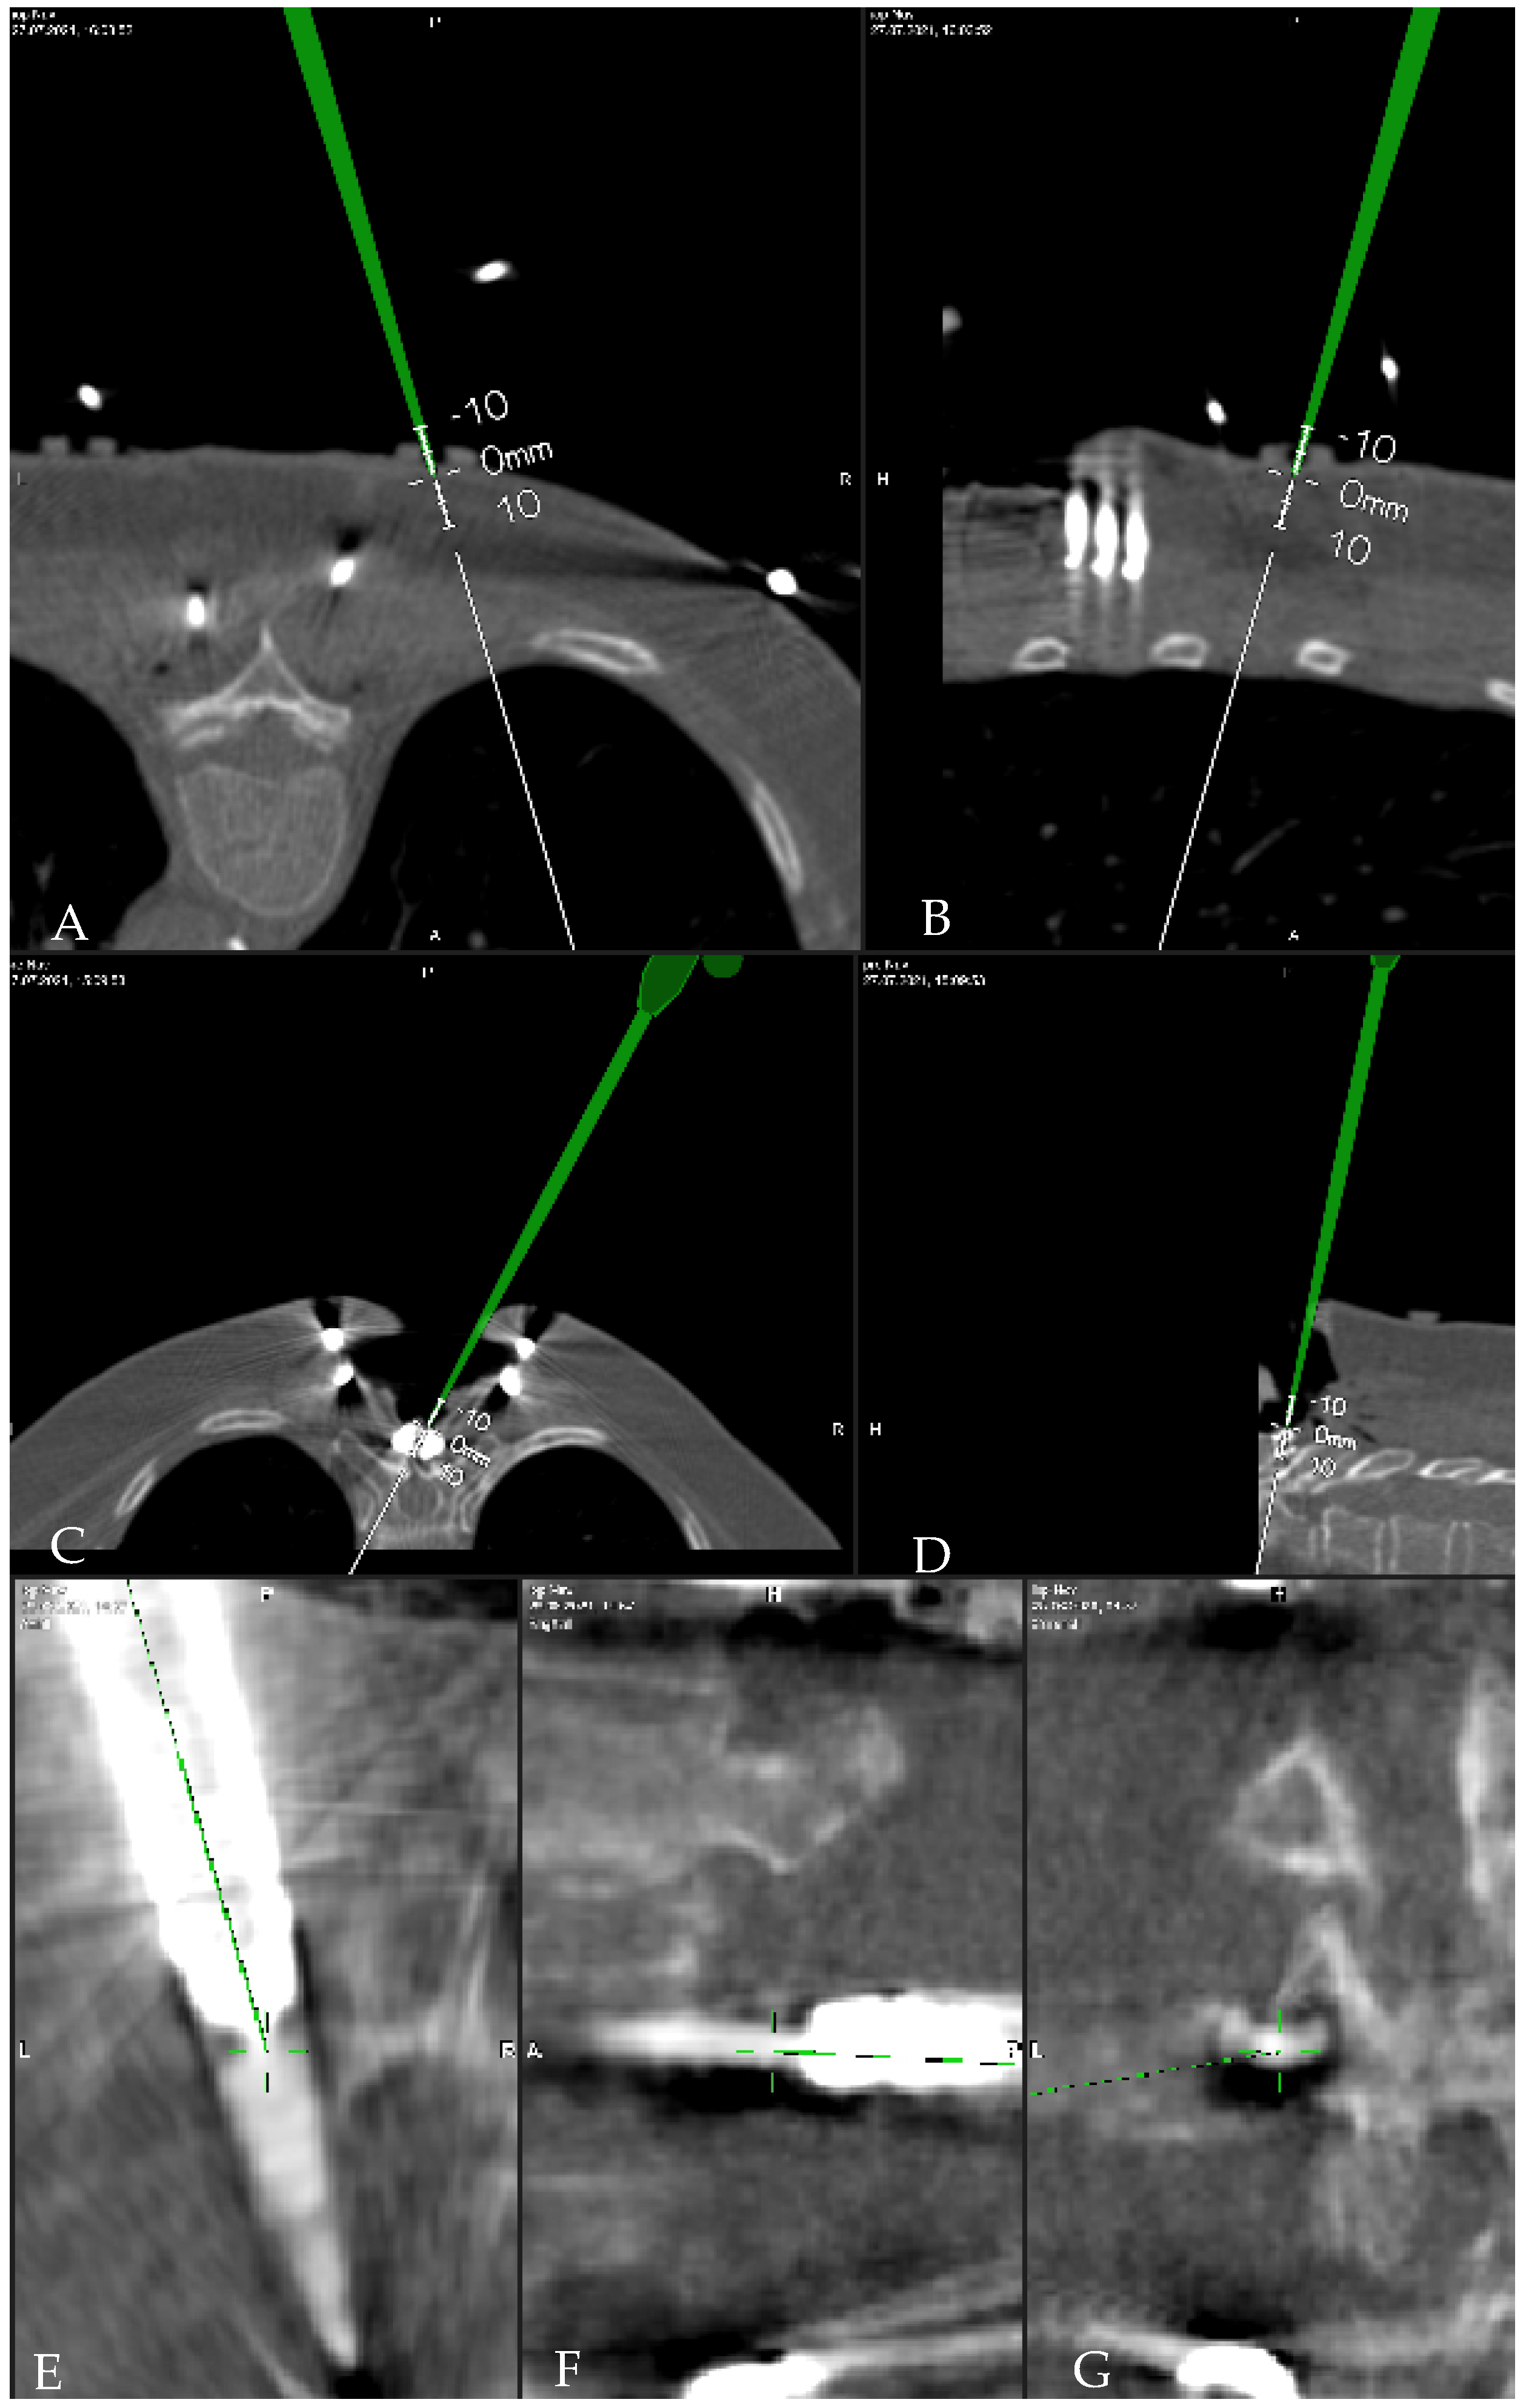

- Pedicle size—measurement of the pedicle size in the axial, coronal and sagittal plane, on the registration iCT scan, with a line perpendicular to the preplanned screw

- Deviation of preplanned trajectory from actual pedicle screw position—offset of the screw compared to preplanned trajectory (degrees to medial/lateral): mean deviation in entry point, the average deviation from the tip of the screw, and angular deviation. Deviations were determined using an image-overlay analysis to compare preoperative CT imaging with preplanned screw trajectories to a true screw position on intraoperative, control CT imaging (Figure 6). The mean deviation of entry point and the average offset from the tip of the screw were measured in the axial plane by determining the perpendicular distance of the midline of the planned screw versus the midline of the actual screw position; this latter line was drawn manually in the software as a best estimate on the slice with the widest screw diameter. Angular deviation was measured by determining the angle of the midline for the planned screw versus the midline of the actual screw position in the lateral plane.